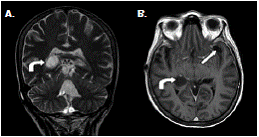

Ante la sospecha de vómito de origen central, se practicó una resonancia magnética cerebral que evidenció múltiples dilataciones de las cisternas y obstrucción del cuarto ventrículo (figura 3) y (figura 4); el líquido cefalorraquídeo tenía aspecto claro, 13 mg/ dl de proteínas, 73 mg/dl de glucosa, no presentaba leucocitos, y se registraron 3 eritrocitos por mm3; la tinción de Gram y el cultivo para bacterias resultaron negativos. Asimismo, se hizo una exploración del cuarto ventrículo por craneotomía suboccipital, mediante la cual se detectó aracnoiditis con obstrucción del agujero de Magendie, e inflamación aguda y crónica confirmada por biopsia. Se diagnosticó, entonces, vómito incoercible de origen central, secundario a neurocisticercosis racemosa (sic) y obstrucción del cuarto ventrículo, probablemente por aracnoiditis grave.

Según los hallazgos en las imágenes de resonancia magnética cerebral, los casos informados se clasificaron como neurocisticercosis extraparenquimatosa con quistes racimosos en el espacio subaracnoideo asociados a la intensa reacción inflamatoria (figura 1), (figura 4).

En los dos casos que se presentan, la neurocisticercosis racemosa (sic) se acompañó de hidrocefalia y aracnoiditis; en el primer caso, además, se detectó vasculitis de la arteria cerebral media derecha en sus porciones proximales adyacentes a las cisternas de la base y la silviana derecha, relacionada con la presencia de cisticercos (figura 1). En el segundo caso, se detectó dilatación y obstrucción del cuarto ventrículo por aracnoiditis (figura 3), hallazgo que explica la causa del vómito incoercible, debido a su estrecha relación anatómica con el área postrema (control del vómito).